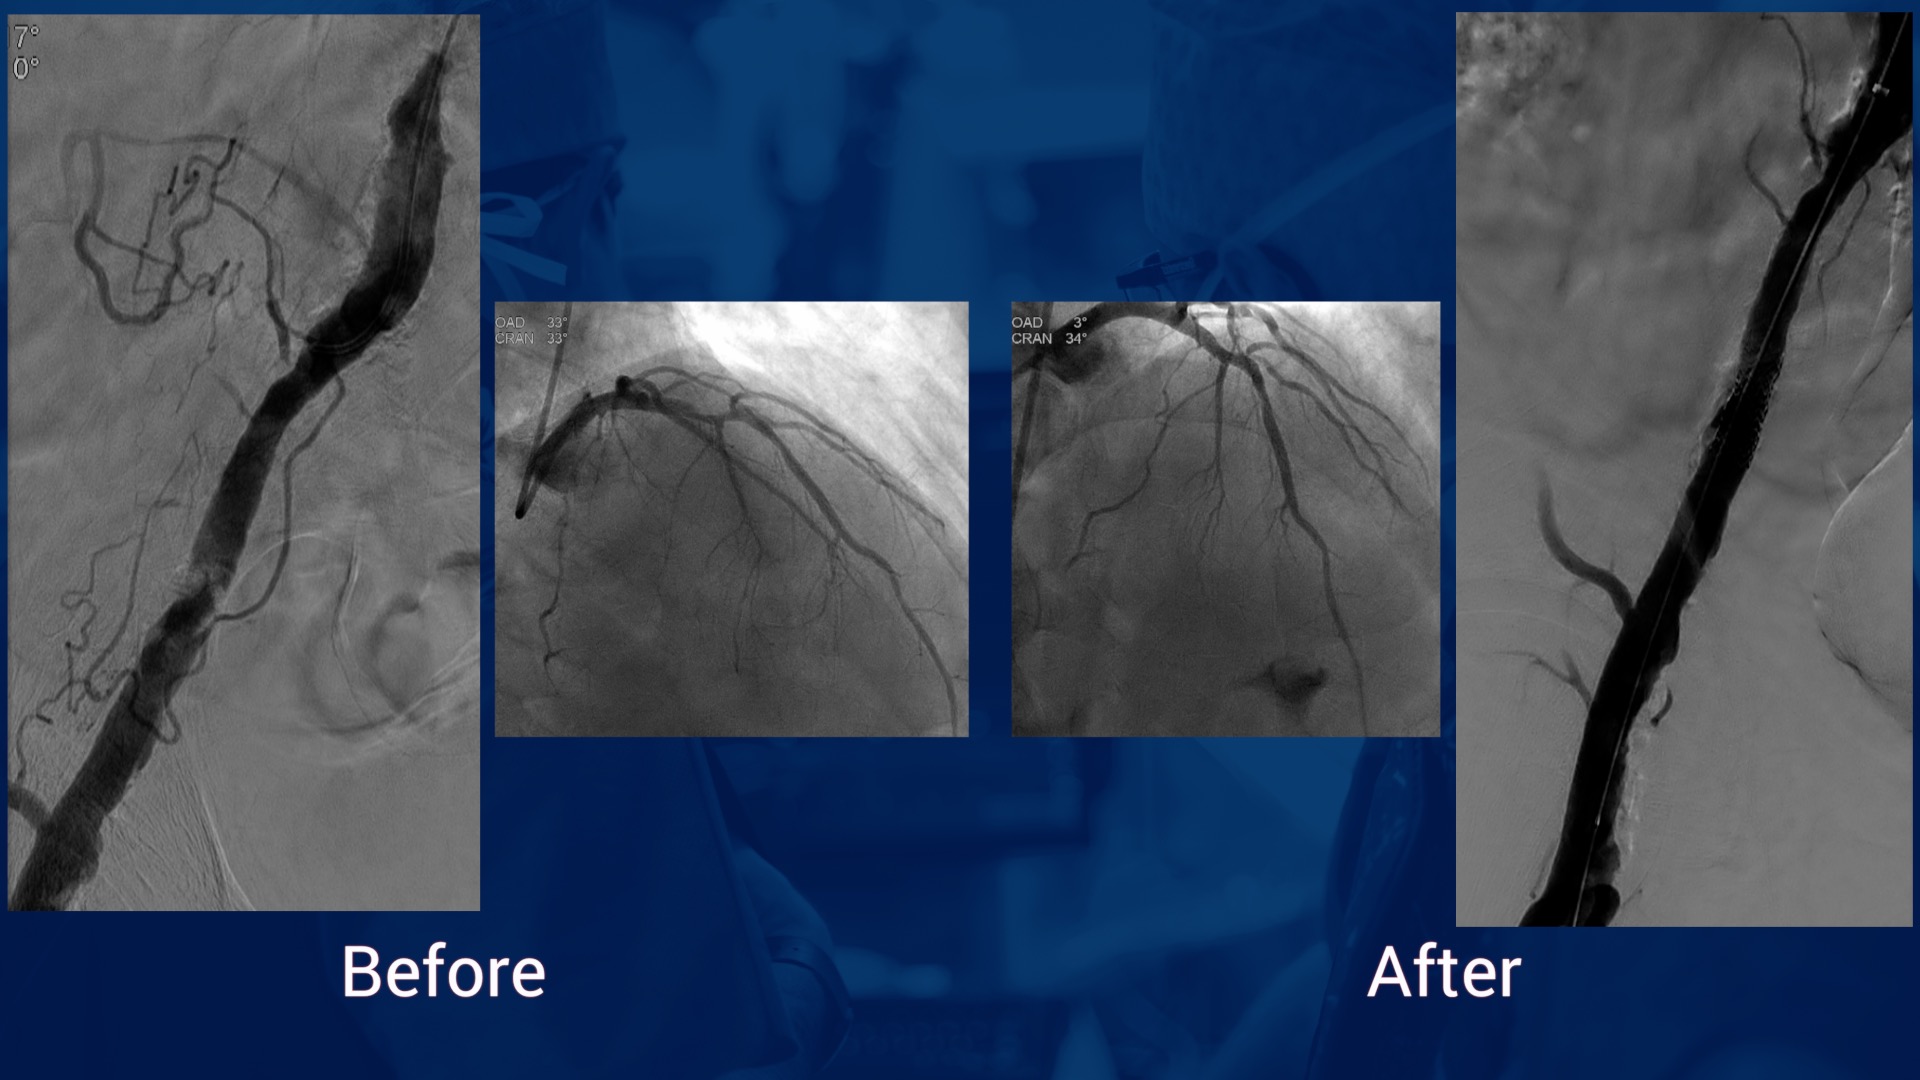

Clinical decision making in patients with high risk of restenosis in Fem- pop: when and how to prepa...

SOLVING UNMET NEEDS in Peripheral Vascular: episode 1